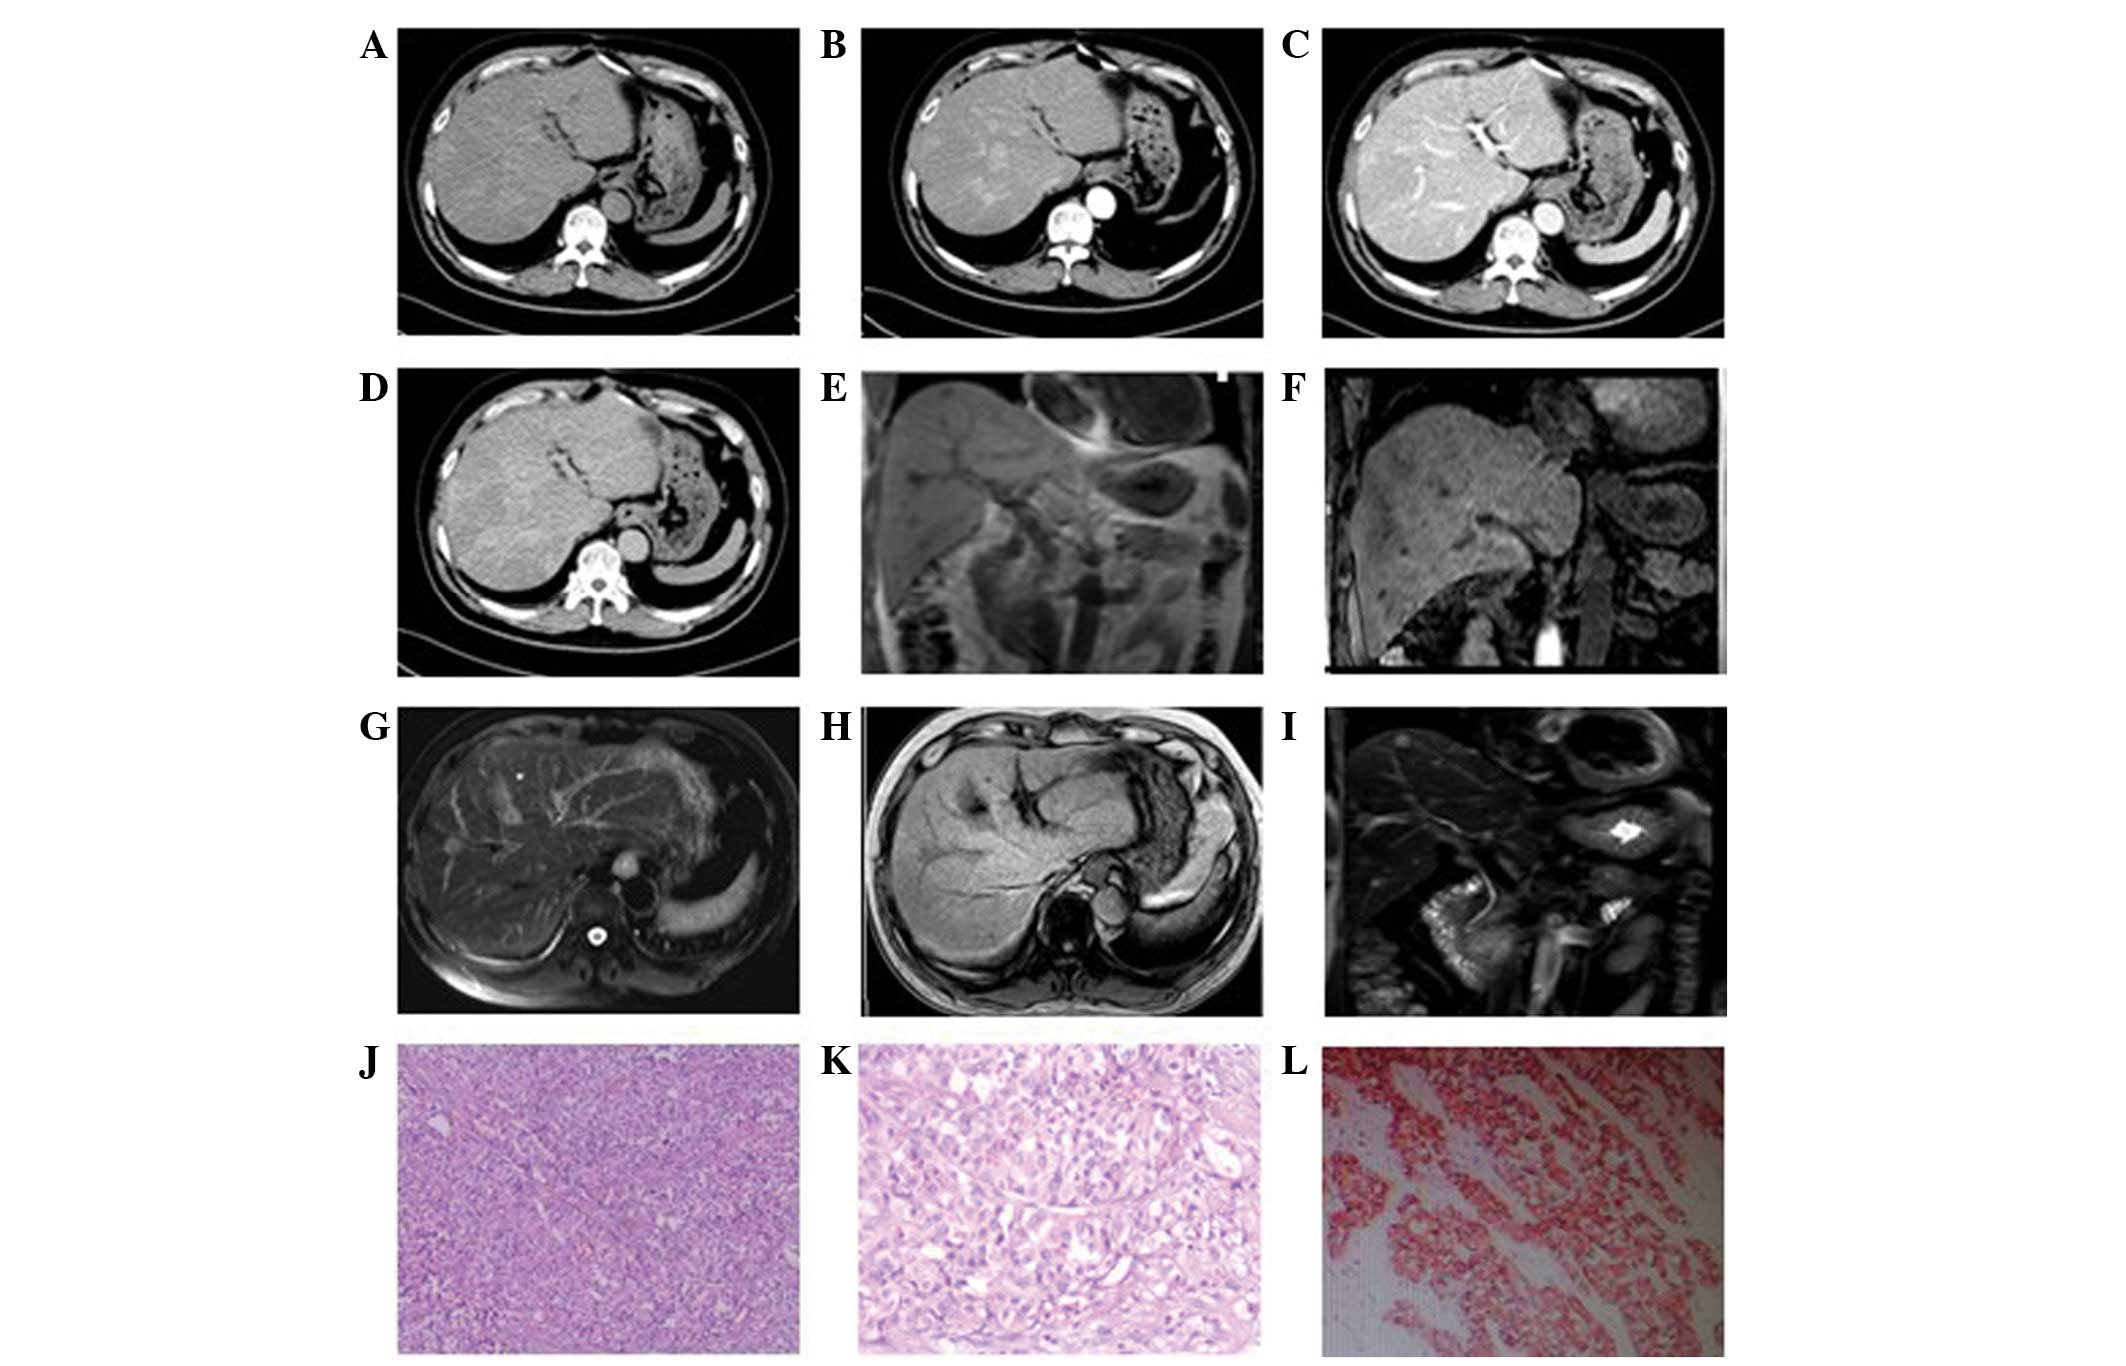

In the eight patients exhibiting multiple intrahepatic lumps, the foci were of various sizes. In four patients, the diameters of the largest foci were >7 cm whilst in the remaining four, the diameters were <2 cm. Plain CT scan showed low-density lesions. The four cases with larger masses had a lower density liquefied necrotic area (Figs. 2A, 3A and 4A) while the four cases with smaller foci had a relatively uniform density (Fig. 5A). The boundaries of the foci were unclear in six patients (Figs. 3 and 5), while they were clear in the other two cases (Fig. 2). All foci showed uneven enhancement in the arterial phase, six of which exhibited annular enhancement (Figs. 2B–4B). In six patients, the degree of enhancement was found to decline in the portal venous phase (Figs. 2C, 3C and 4C) and the delayed phase (Figs. 2D, 3D and 4D). In two patients, the enhanced area was enlarged in the portal venous phase (Fig. 5C) and the enhancement extended over a long period of time. The degree of enhancement in the delayed phase (Fig. 5D) declined in all cases, and the density of the foci was generally uniform. In one patient (Fig. 6), the foci were not observed in plain scanning but were clearly observed in the arterial phase and absent in the portal venous and delayed phases.

Figure 6

Poorly differentiated neuroendocrine carcinoma in a 57-year-old male. Foci were (A) not visible in plain computed tomography, (B) were clearly visible in the arterial phase and (C) disappeared in the portal venous and (D) delayed phases. No multiple intrahepatic nodules were observed in (E) magnetic resonance imaging T1- and (F) T2-weighted images. Relatively long signals were observed in (G) T2-weighted fat suppression and (H) T1 enhancement images. (H) The foci were unevenly enhanced in T1 enhancement scanning. (J and K) HE staining (magnification, ×100 and 200, respectively) and (L) immunohistochemical staining revealed a number of tumor cells to be uniformly small- to medium in size, with unclear cytoplasmic boundaries and round and regular nuclei arranged flakily, uniformly and in clusters, or like a chrysanthemum.

MRI results

Two patients were subjected to MRI. In one case (Fig. 2E–J), multiple long T1 and T2 signal foci were observed in the liver, which were nodular, lumpy and significantly enhanced. Another patient (Fig. 6E–I) exhibited multiple intrahepatic nodules that were not clearly visible in T1- or T2-weighted images. However, a relatively long signal was observed in T2-weighted fat suppression and T1 enhancement images. In addition, the foci were unevenly enhanced in T1 enhancement scanning.

Pathology

A number of different types of neuroendocrine tumor were observed in this study, including carcinoid tumors, a well-differentiated neuroendocrine carcinoma and a poorly differentiated neuroendocrine carcinoma. Among these were two cases of carcinoid tumors (Fig. 3E and 3F), three cases of well-differentiated neuroendocrine carcinomas (Figs. 2K and 5E) and four cases of poorly-differentiated neuroendocrine carcinomas (Figs. 1F, 4E and 6J–L). Pathological results showed that the tumor cells were morphologically diverse and that a number of tumor cells formed vessel-like arrangements, with similar morphological features and of little interstitial substance (Figs. 2K, 3E and 3F). Other tumor cells were uniformly small- to medium in size with unclear cytoplasmic boundaries. Additionally, their nuclei were round or regular in shape and arranged irregularly, clustered and flakily or like a chrysanthemum (Fig. 6J–L). The poorly differentiated cancer cells were smaller and with less cytoplasm than the well-differentiated cells. Their nuclei were angular, trachychromatic and karyokinesis was observed (Figs. 1F and 4E). In addition, neuroendocrine granules were observed by electron microscopy (H-7500 Electron Microscope, Hitachi, Tokyo, Japan). The immunohistochemical staining in these tumor cells was positive for CgA and Syn and negative for CEA, HPC and AFP (Table I).